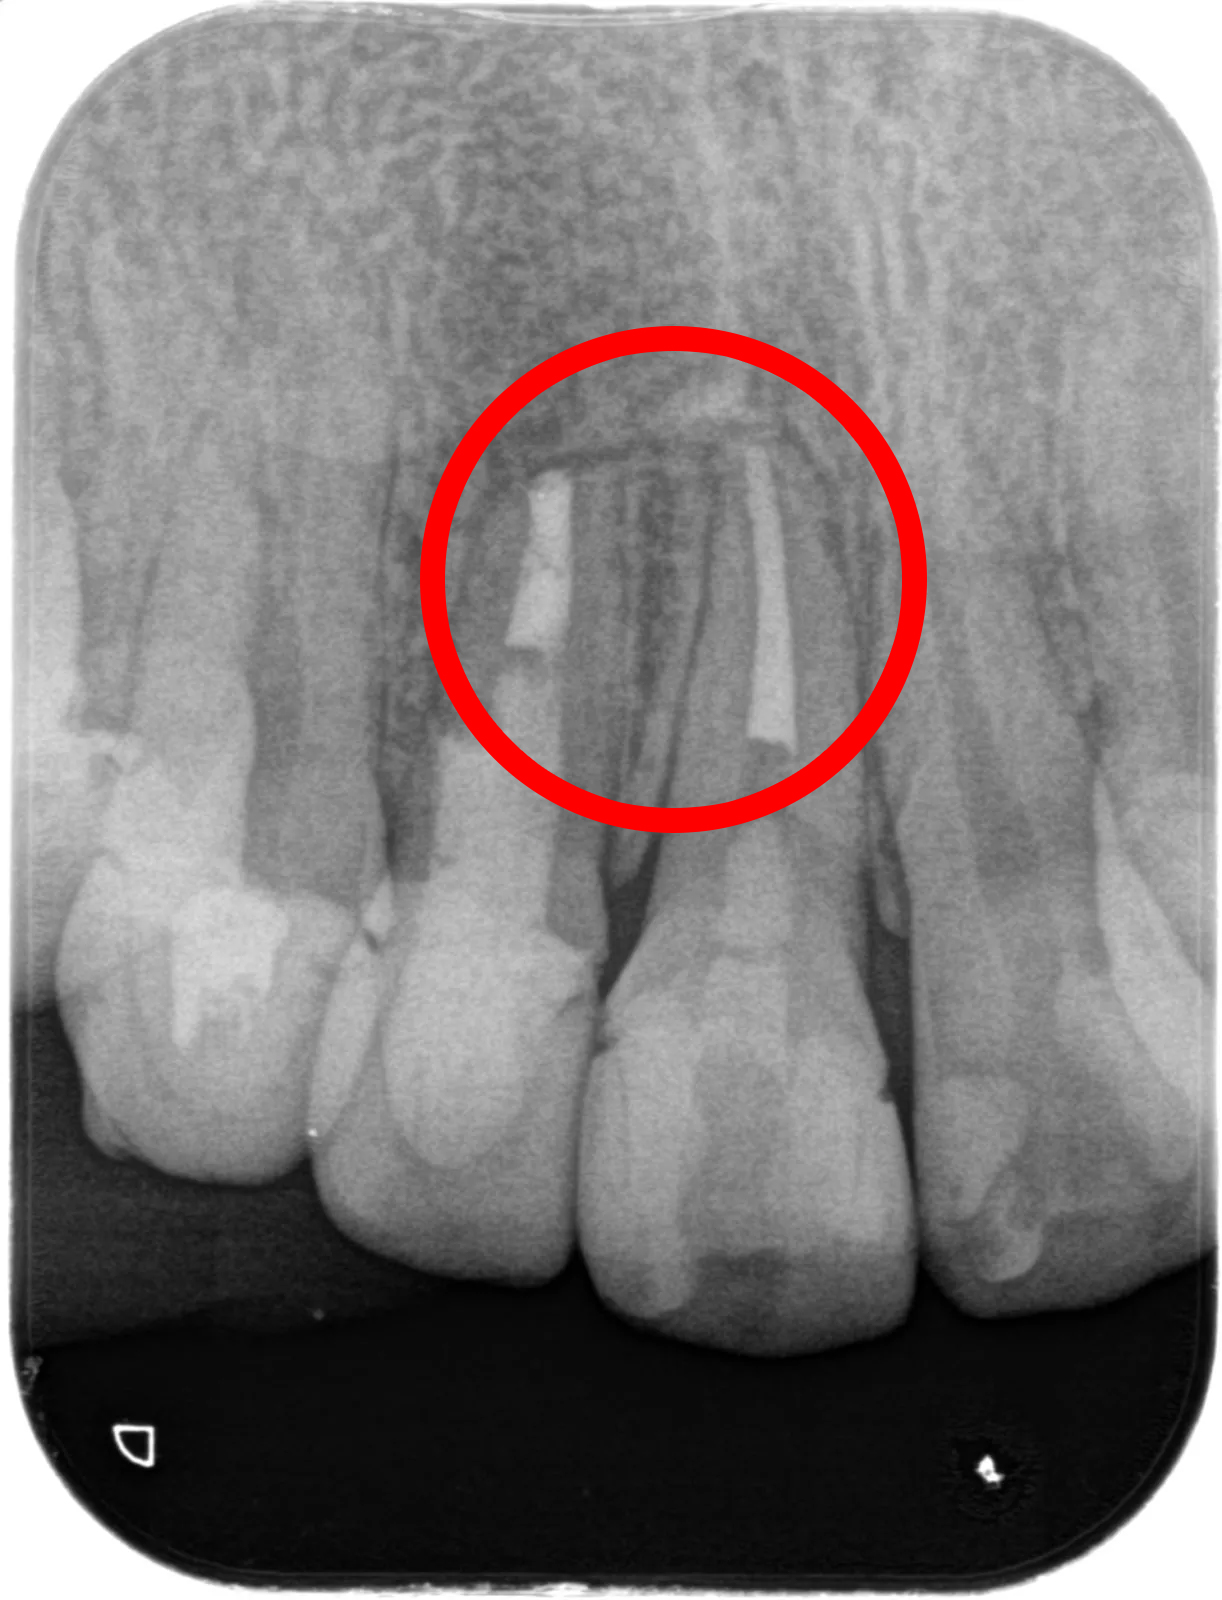

• 治療前

• 治療後

■主訴:他院で治療した右上の前歯にズーンとした違和感がある たまに噛むと痛い

■詳細:当院の歯内治療専門医による歯根端切除術(外科的歯内療法)。歯根端を切除、逆根管形成後MTAを充填。

■治療期間:治療開始からは一回の来院のみ、一時間半ほど。

■治療費:14.3万円 (当医院で二年以内に自費根管治療している場合は半額)

■治療のリスク:歯根が短くなることにより動揺が出る恐れがある